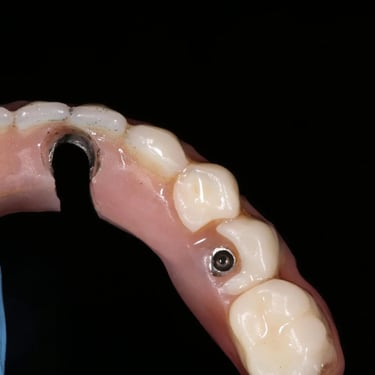

Fractura de la prótesis sobre implante

La fractura de la prótesis sobre implante es una ruptura o daño en la corona, puente o dentadura soportada por implantes.

Los pacientes pueden notar una prótesis suelta o dañada.

El tratamiento incluye la reparación o reemplazo de la prótesis afectada